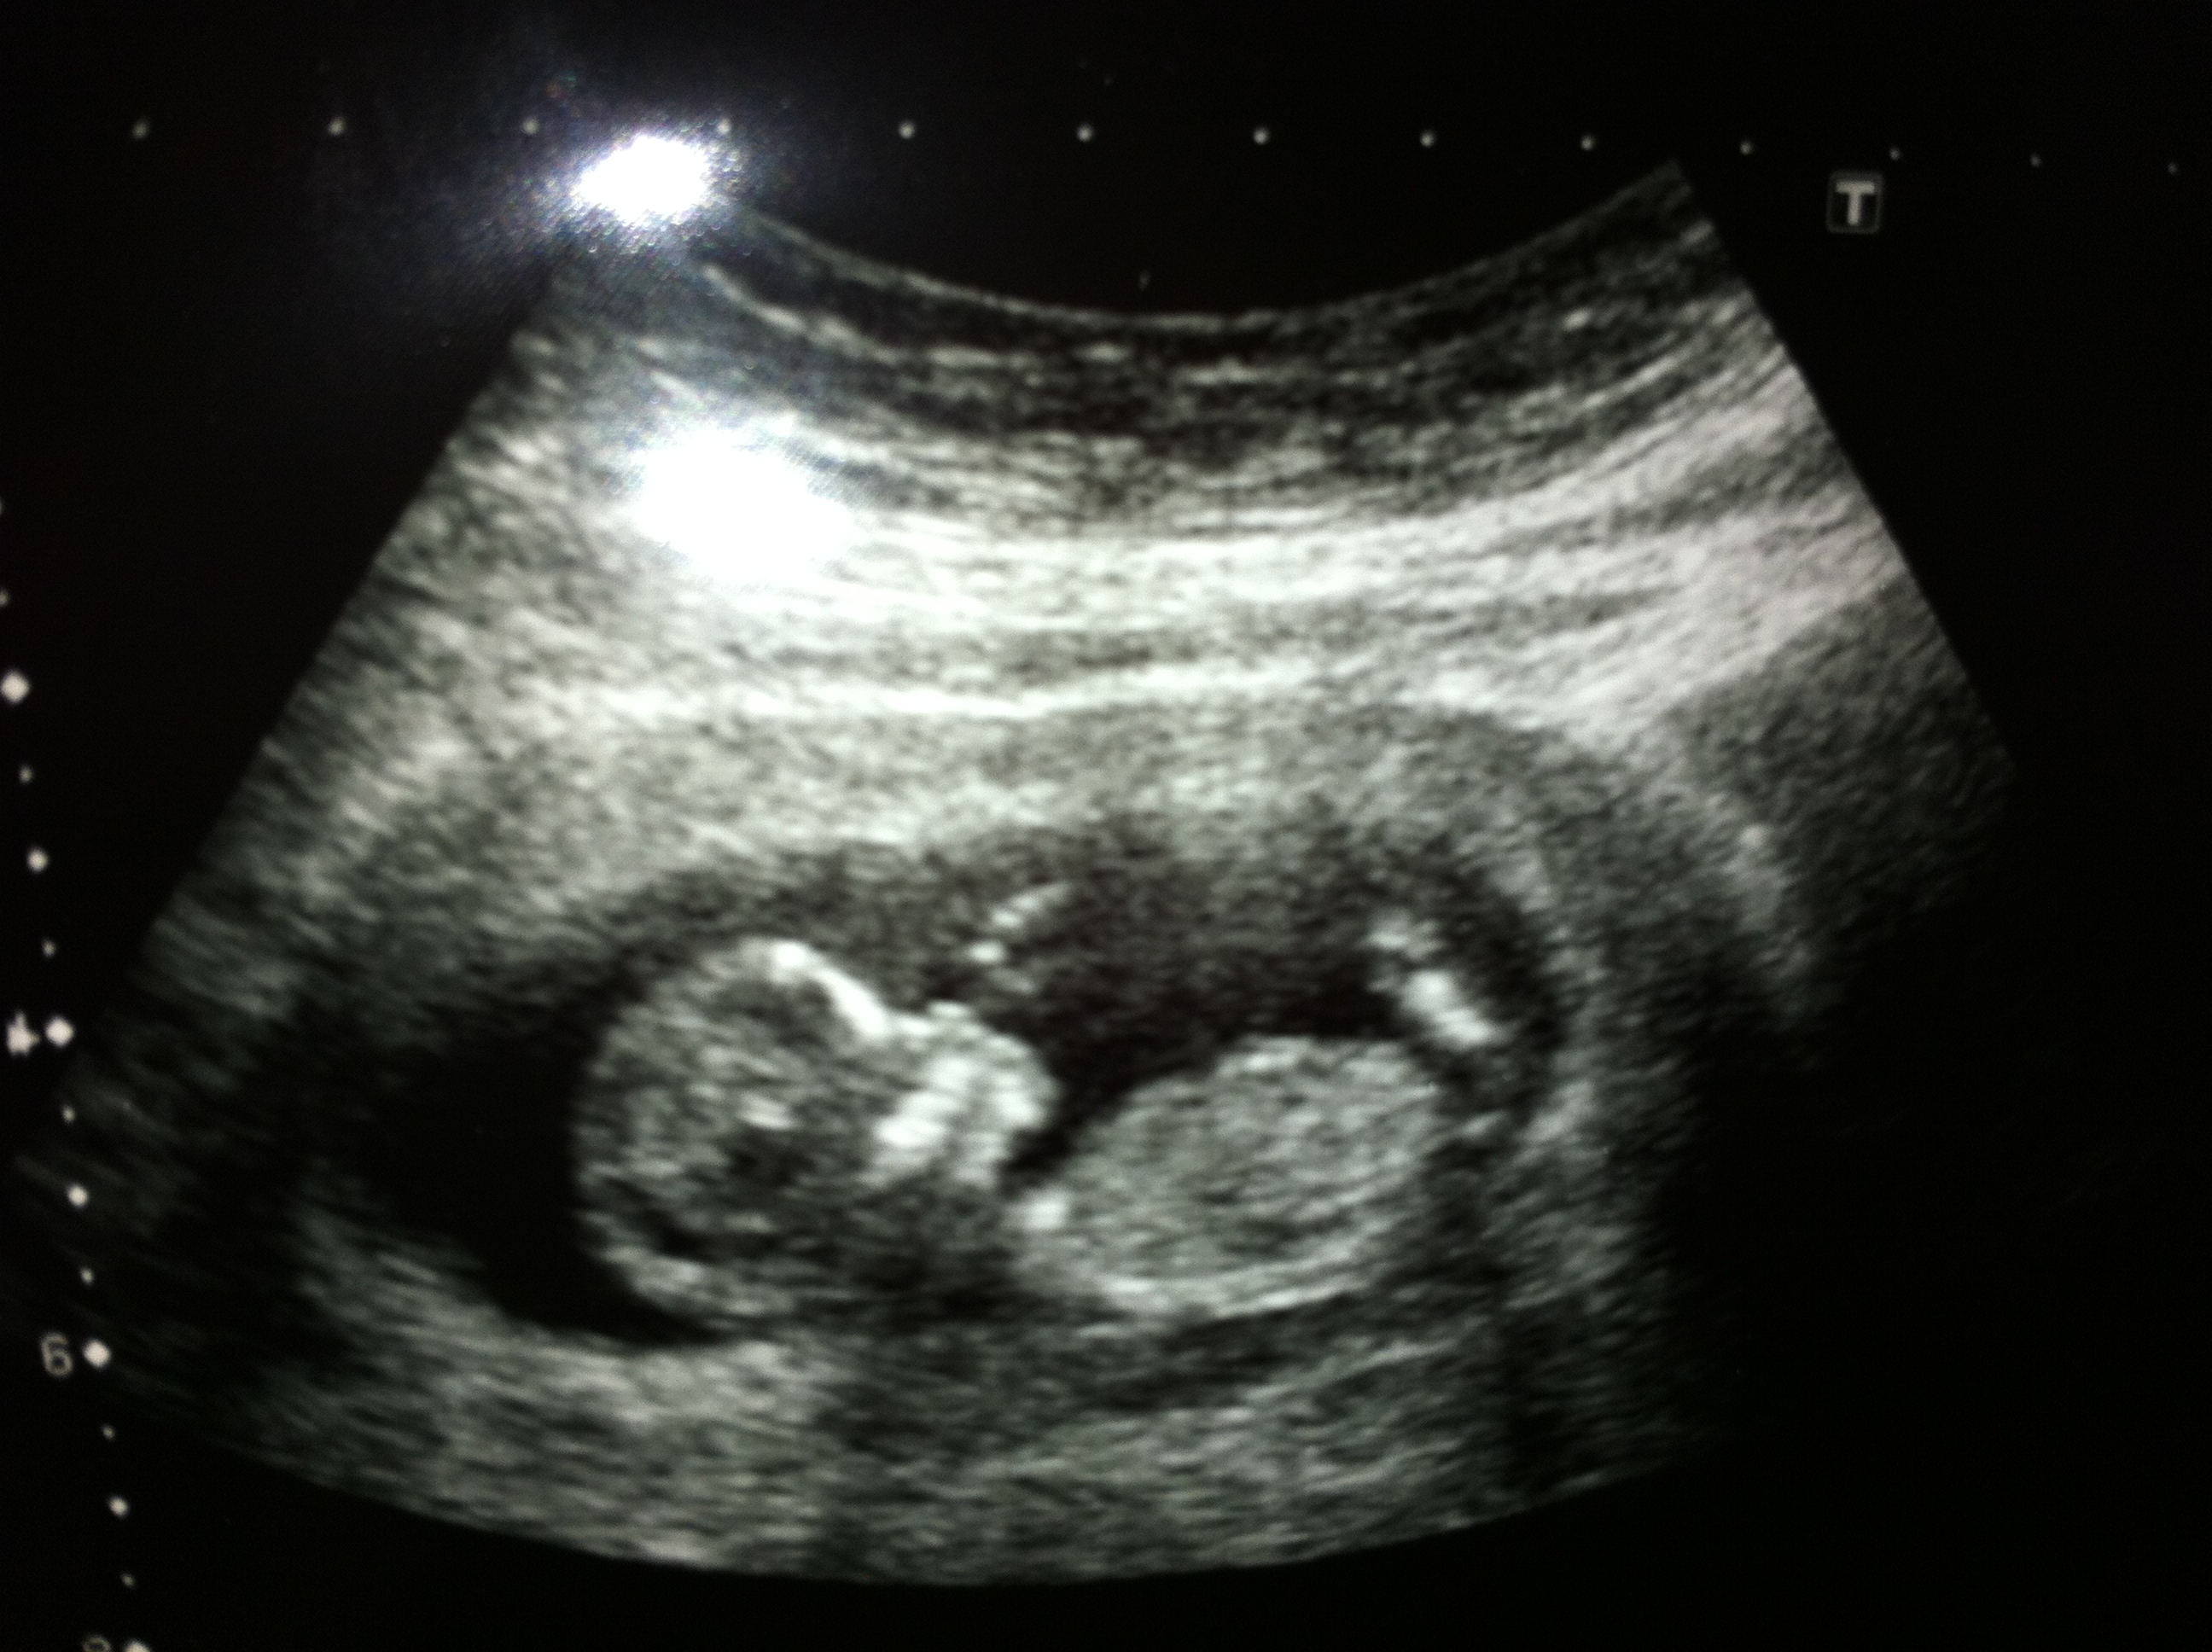

My fiancee is going out of her head wanting a girl - what are your thoughts?

I'm no nub expert and not sure if what I see is a nub but my guess is girl :)

if what we are seeing is the nub i would lean girl to. What gestation were these taken at (as that effects the accuracy) and do have any more for comparison?

The picture was taken at 12 weeks 4 days. No more pictures unfortunately

Just letting you know that it was confirmed today that we are expecting a girl :baby: